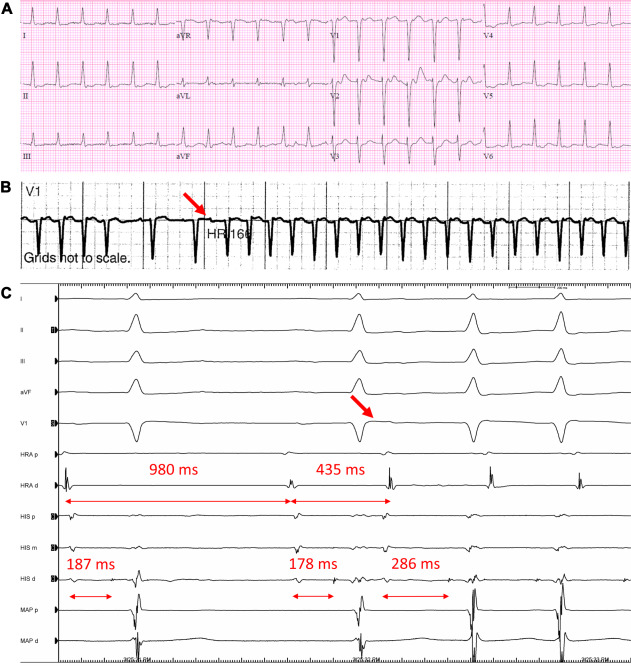

One of the more fascinating presentations of Lyme carditis that I’ve seen here in Western Pennsylvania. Heart Rhythm Case Reports heartrhythmcasereports.com/article/S2214-…

A truly collaborative, multidisciplinary effort with University of Pittsburgh colleagues to produce this manuscript on catheter ablation of macro-reentrant atrial tachycardia in adults with Ebstein anomaly. heartrhythmopen.com/article/S2666-…

Pulsed field ablation in persistent left superior vena cava for atrial fibrillation via interrupted inferior vena cava with azygos continuation utilizing novel electroanatomic mapping features in the presence of a permanent pacemaker Norman C. Wang, MD, MS heartrhythmcasereports.com/article/S2214-…

Pulsed field ablation in persistent left superior vena cava for atrial fibrillation via interrupted inferior vena cava with azygos continuation utilizing novel electroanatomic mapping features in the presence of a permanent pacemaker